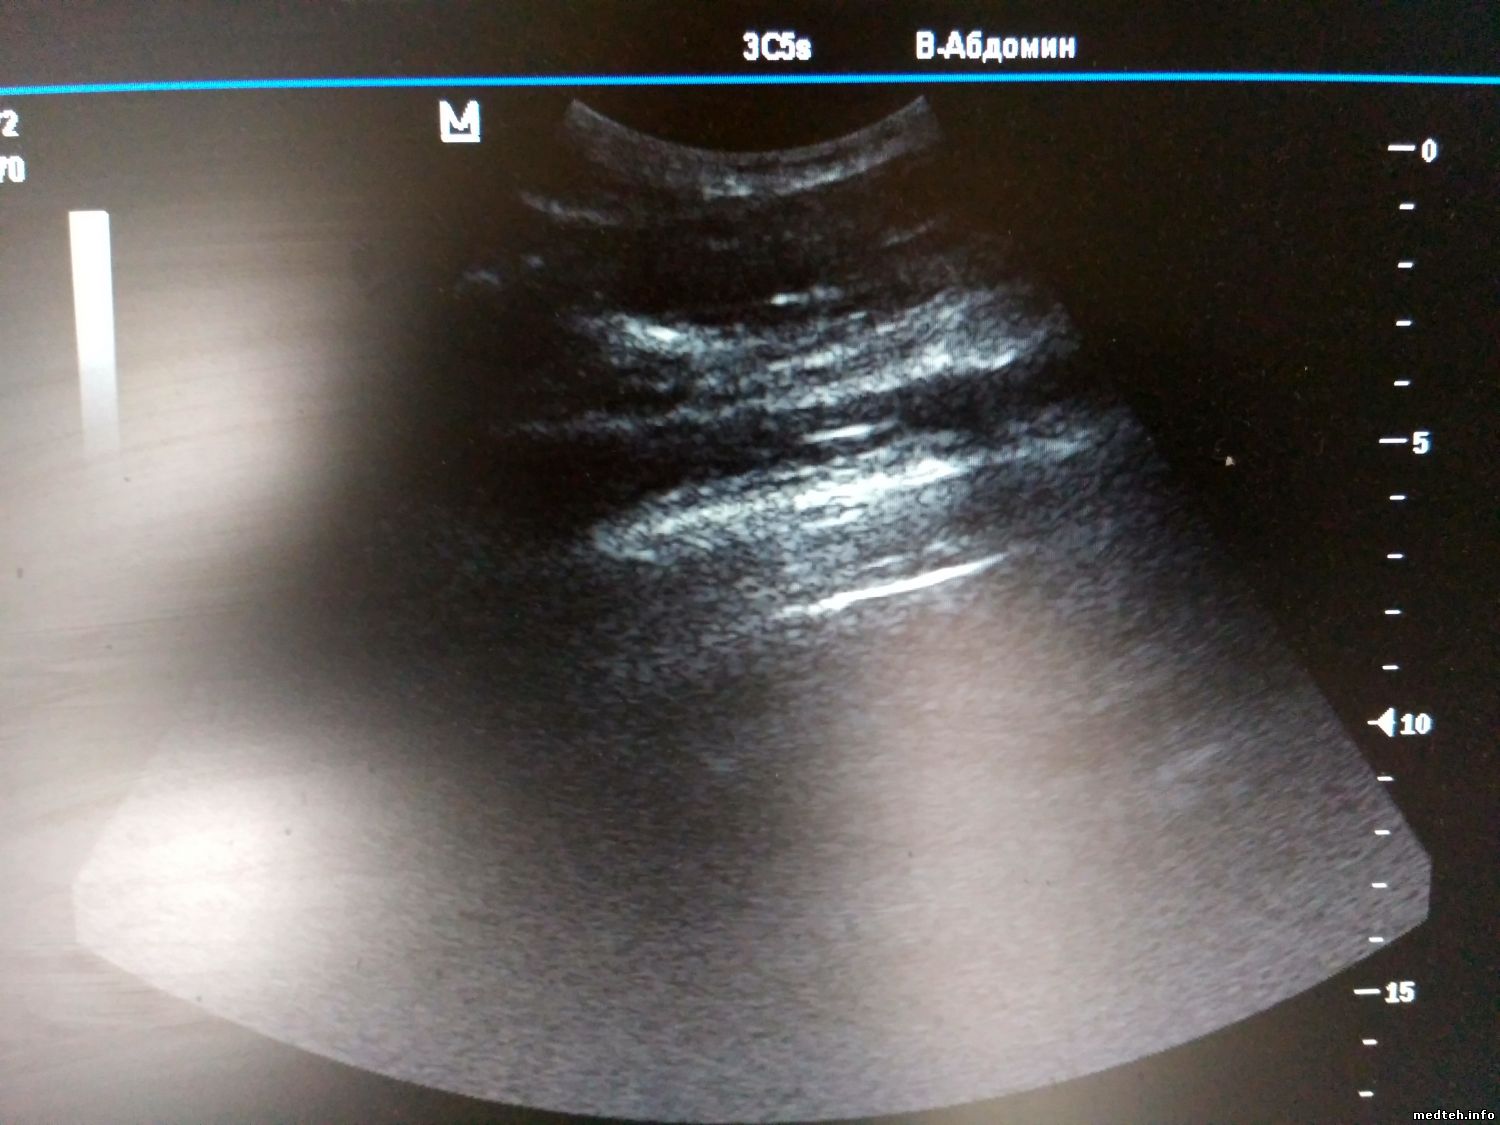

У Mindray M5 появились затемнения в виде двух полосок, которые срастаются в пятно по центру, при этом такая картина идентична на разных видах датчиков. Когда конвексный подключил к другому Миндрею М5, то там всё нормально.

Разъёмы смотрел, окиси нет, не гнутые.

Может есть калибровки или это железо глючит?

8885968.jpg (156.5 Kb)

Просто последний был конвексный. На первом фото полосы есть, на втором их нет (датчик один и тот же, аппараты разные).

1762746.jpg (148.7 Kb) · 7828479.jpg (158.8 Kb)